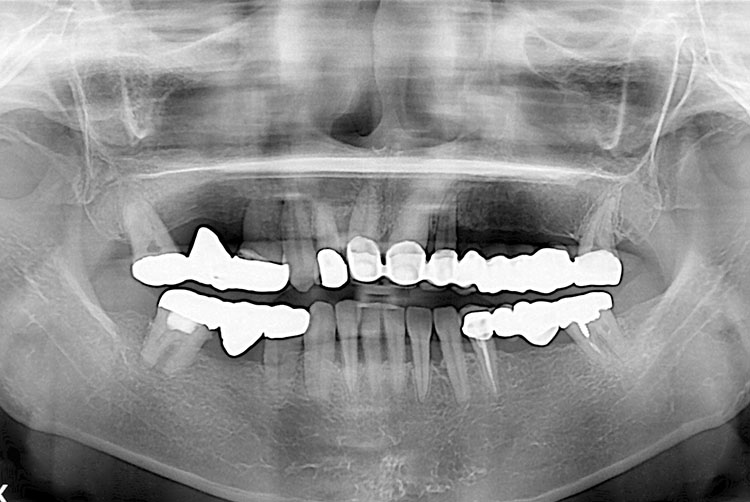

[임플란트] 임플란트

치료후 : 2019-12-21

세종치과는 많은 환자와 다양한 케이스를 바탕으로 항상 편안한 임플란트 수술을 제공하고자 노력하고,

오래동안 튼튼히 쓸 수 있는 임플란트 수술을 가장 큰 목표로 삼고 있습니다